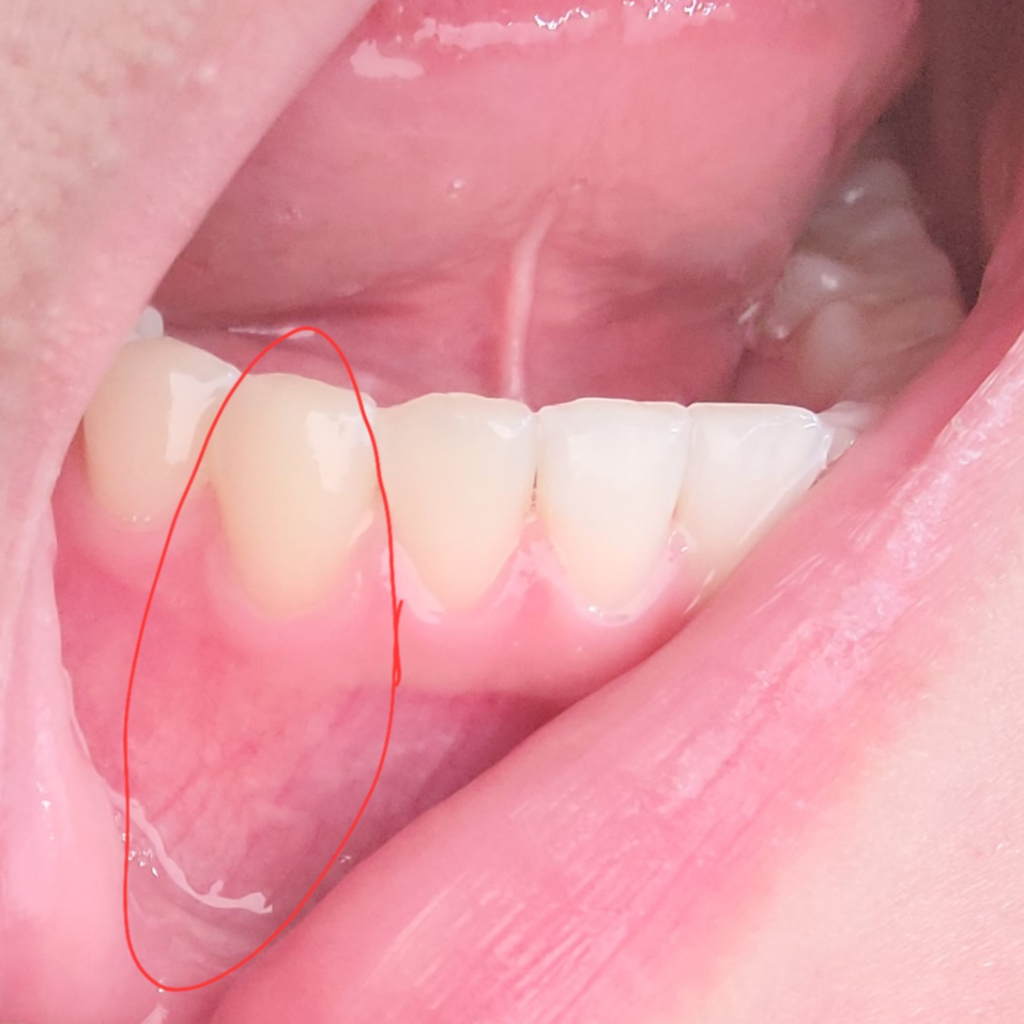

이빨 밑 잇몸 안쪽이랑 바깥쪽이 엄청 아파요

진짜 미친듯이 욱씬거리는데 충치도 없고 치석 때문인가 싶어서 4일 전에 스케일링도 받고 왔습니다 치위생사님이 피가 좀 났다고는 하셨는데 어디서 났는지는 모르겠어요 근데 스케일링 받고 4일이나 지났는데 더 아픕니다ㅠㅠ 치석 때문이 아니었나 아니면 스케일링 이후 치석이 많았으면 원래 좀 통증이 있나요? 근데 진짜 말도 안나올 정도로 아프기 시작해요 6시부터 ㅠㅠ 내일 치과 갈건데 진짜 너어어어어어무 아파요ㅠㅠ 왼쪽 턱까지 아프고 미치겠어요ㅠ 왼쪽 아프다가 오른쪽 아프고 왼쪽 아프다 오른쪽 아프고 또 이빨은 세트로 똑같은 곳만 아파요 아랫니 4개 중심으로 붙은 양쪽들이 왼쪽 아팠다가 오른쪽 아팠다가 환장하겠네요 근데 지금 왼쪽에 통증이 너무 심해서 올려봅니다ㅠㅠ

• 1번 째 사진

사진으로는 크게 문제가 없는 것으로 보입니다 통증이 해당 부위에 지속이 된다면 해당 부위로 너무 강한 음식을 드시지 않았는지 확인해 보시고 아무런 이상이 없음에도 불구하고 통증이 있다면 신경병증인 원인일 수도 있습니다 치과에서 구강내과에서 진료를 받아 보는 것을 권해 드립니다